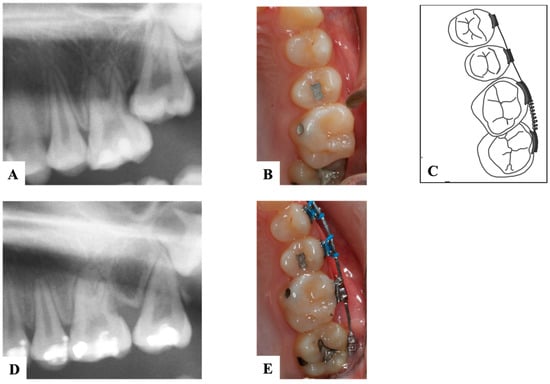

9.2. Distal Tipping